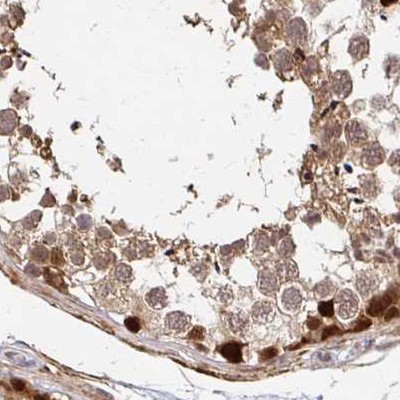

Immunohistochemical staining of human cerebral cortex, colon, kidney and testis using Anti-PSMD7 antibody HPA049824 (A) shows similar protein distribution across tissues to independent antibody HPA056069 (B).